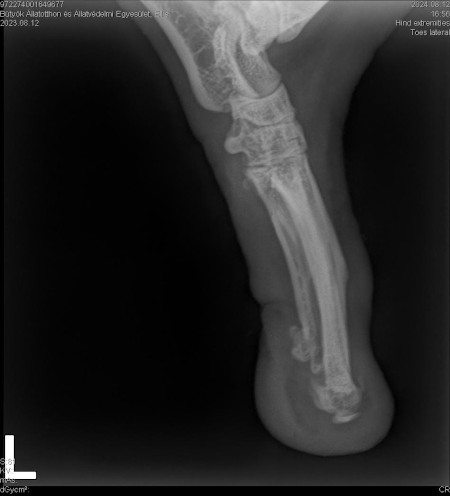

| Bemerkungen | Ellie fehlt am linken Hinterbein der Fuss/die Pfote |

Ellie ist ca. 1 Jahr alt (Stand 08/2024) und hat bereits eine bewegte Vergangenheit hinter sich. Nach 5 Tagen intensiver Versuche konnte sie endlich von der Strasse gerettet werden, wo sie hungrig, durstig und in einem schlechten gesundheitlichen Zustand allein und orientierungslos umherirrte. Elli war von Flöhen und Zecken geplagt und stark abgemagert, doch trotz all dieser Herausforderungen zeigt sie einen unglaublichen Lebenswillen. Elli hat ein Handicap: Ihr fehlt ein Fuß am Hinterbein. Ob dies auf einen Unfall oder eine angeborene Fehlbildung zurückzuführen ist, wissen wir nicht. Doch Elli lässt sich davon nicht einschränken! Sie zeigt sich flink und steckt voller Energie. Ellie kommt erstaunlich gut mit ihrem Bein zurecht, es stört sie in keiner Weise und sie kann problemlos laufen, spielen und sogar rennen. Dennoch benötigt sie einen Schutz für ihren Stummel, entweder eine passende Prothese oder einen gefütterten Silikonschuh. Dies sollte in ihrem neuen Zuhause gründlich tierärztlich abgeklärt werden. Trotz ihrer Vergangenheit ist Elli eine unglaublich liebe, verschmuste und fröhliche Hündin. Sie liebt die Nähe zu Menschen, ist sehr anhänglich und versteht sich gut mit anderen Hunden. Ihre neuen Menschen sollten Freude daran haben, ihr alles ruhig und geduldig beizubringen, was so ein junges Mädel für ihr weiteres Leben als Familienhündin wissen muss. Ebenso sollten sich die neuen Besitzer bewusst sein, dass ein Hund nicht nur Freude, sondern auch jede Menge Arbeit und Verantwortung mit sich bringt, damit Ellie sich zu einer tollen Begleiterin entwickeln kann. Für unsere Herzensbrecherin suchen wir ein liebevolles, fürsorgliches und dauerhaftes Zuhause, wo sie nebst viel Spass auch abwechslungsreiche Spaziergänge erleben darf, wo sie artgerecht ausgelastet wird und täglich die Zuwendung und Pflege bekommt die sie verdient. Wer erfüllt den Traum von unserer Zuckerschnute Ellie und gibt ihr trotz ihres kleinen Handicaps die Chance ein treues Familienmitglied zu werden?